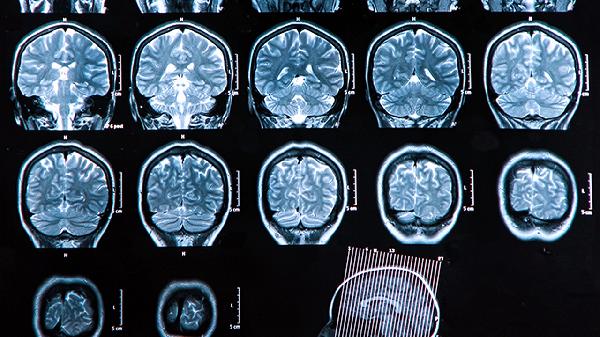

不明原因的站立不稳、步态蹒跚,甚至突然跌倒但意识清醒,提示小脑或脑干缺血。高龄患者伴随高血压时风险更高,建议进行头颅MRI检查,日常使用拐杖辅助行走,医生会根据情况使用尼莫地平片扩张脑血管。